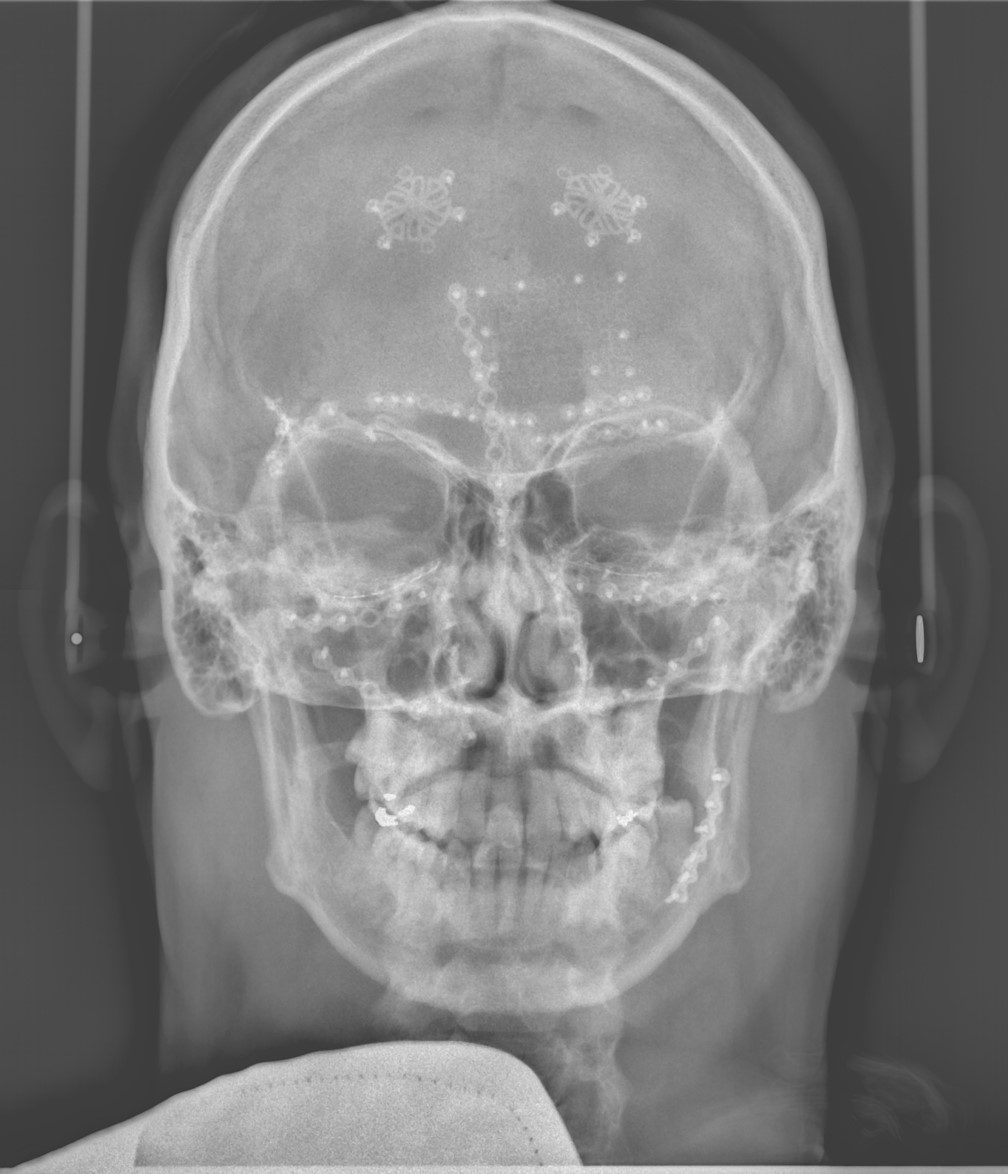

Les spécialistes en chirurgie buccale et maxillo-faciale ont la formation nécessaire pour traiter les patients ayant subi un traumatisme facial. La traumatologie maxillo-faciale comprend tout les types de fractures des os du visage, du front au menton, en incluant les plaies ou lacérations de la peau et des tissus mous, ainsi que les traumatismes dento-alvéolaires.

Les fractures les plus fréquentes sont celles de la mandibule (mâchoire inférieure), celle du tiers moyen du visage (maxillaire supérieur, os malaire, plancher de l’orbite).

La consultation initiale est généralement faite en milieu hospitalier. La chirurgie pour traiter les fractures est faite sous anesthésie générale. Une hospitalisation de courte durée est nécessaire dans la majorité des cas. Les cas plus complexes pourraient nécessiter une période d’hospitalisation plus longue.